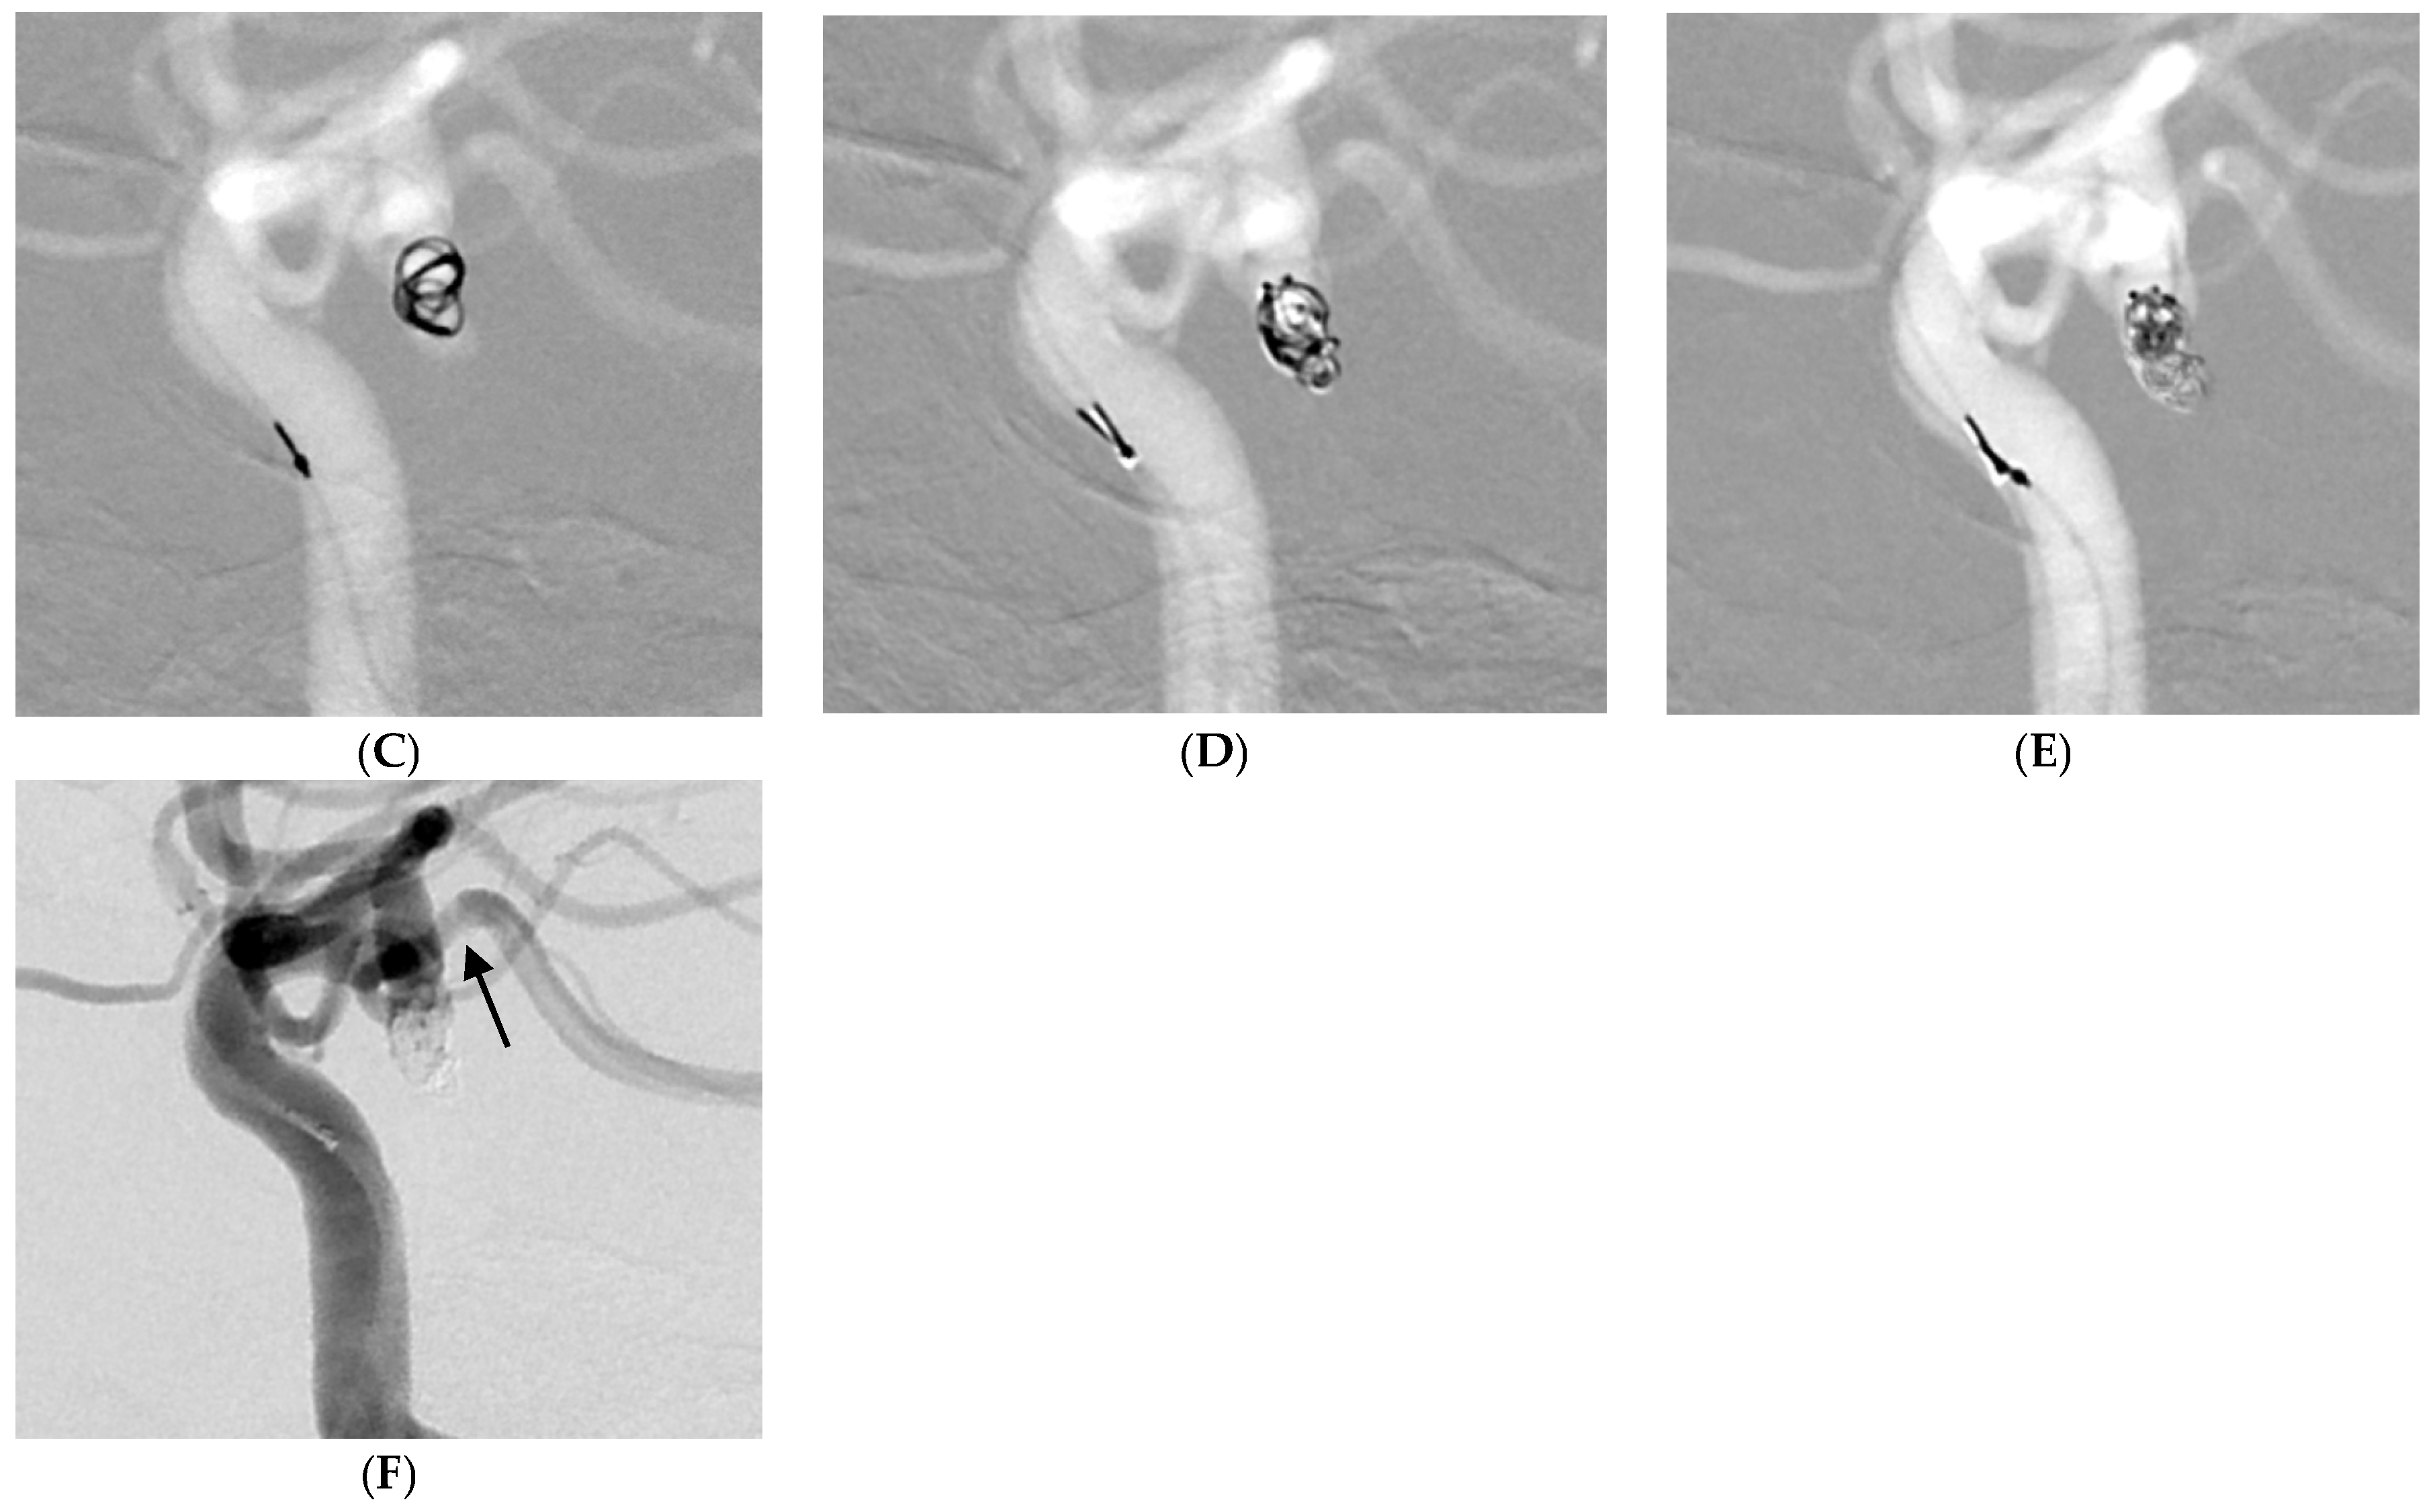

Figure 3.

A 74-year-old female patient with a ruptured left posterior communicating artery aneurysm. (A,B) Three-dimensional rotational angiography shows a left posterior communicating artery aneurysm (neck: 3.1 mm, height: 4.7 mm, size: 3.9 × 3.5 mm). (C–E) The patient was treated with five target tetra detachable coils using a double microcatheter technique. (F) Postprocedural angiography showing complete occlusion of aneurysm (Raymond and Roy Occlusion Classification I) with preservation of the posterior communicating artery (arrow).